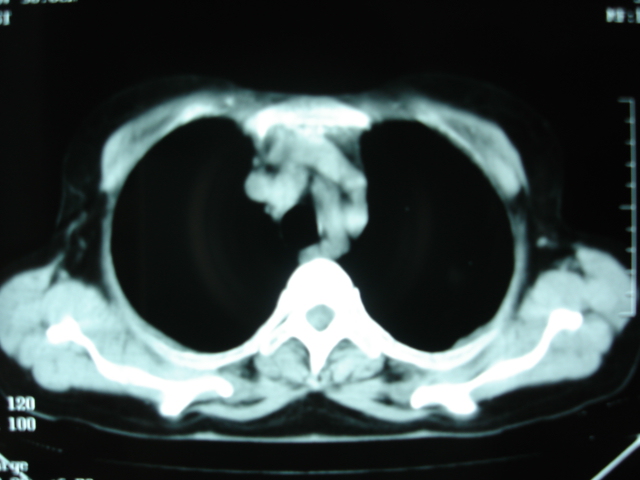

以下是引用卜一在2009-9-7 19:51:00的发言:[br][br] 1 左侧胸内甲状腺占位-多考虑甲状腺腺瘤! 2、左肺门占位-建议增强扫描以便明确性质。 3 慢支并感染! [br]

以下是引用shibing在2009-9-7 20:40:00的发言:[br]左侧胸内甲状腺占位-多考虑甲状腺腺瘤! 2、左肺门占位-建议增强扫描以便明确性质。 3 慢支并感染! [br]